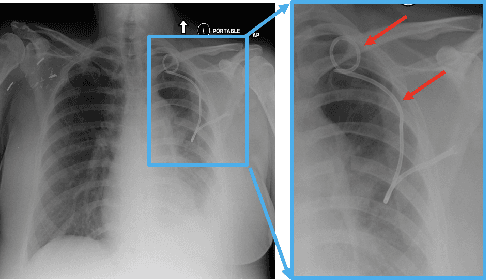

Abstract:Chest x-ray imaging is widely used for the diagnosis of pneumothorax and there has been significant interest in developing automated methods to assist in image interpretation. We present an image classification pipeline which detects pneumothorax as well as the various types of chest tubes that are commonly used to treat pneumothorax. Our multi-stage algorithm is based on lung segmentation followed by pneumothorax classification, including classification of patches that are most likely to contain pneumothorax. This algorithm achieves state of the art performance for pneumothorax classification on an open-source benchmark dataset. Unlike previous work, this algorithm shows comparable performance on data with and without chest tubes and thus has an improved clinical utility. To evaluate these algorithms in a realistic clinical scenario, we demonstrate the ability to identify real cases of missed pneumothorax in a large dataset of chest x-ray studies.